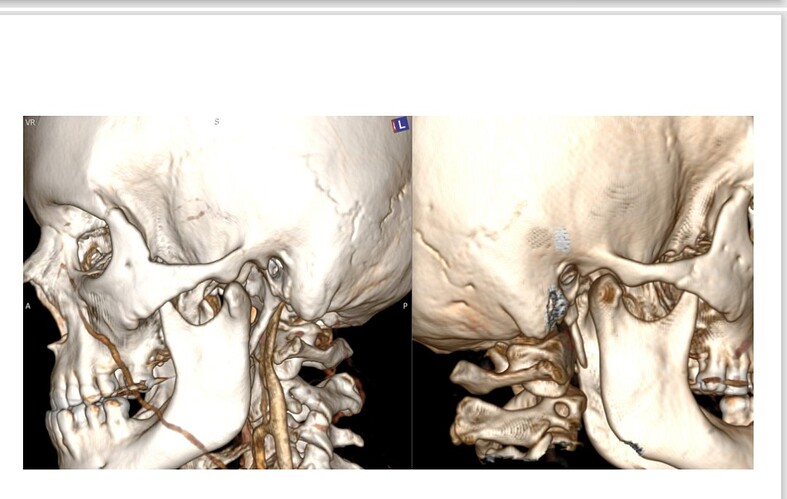

Would it be helpful if I include the radiologist report? It does say there is compression of the internal jugular vein by the styloid process. Please let me know and I will gladly edit my message.

I have edited my post one more time, it must be my anxiety. I have added a picture of my scan with contrast. My elongated styloid processes are trapping my jugular vein. My carotid artery is off track… :scream:

@Hamela - Your styloids aren’t terribly long, but they are exceedingly thick, especially the left one which is a bit more angled than the right one. The right one is more curved. The thickness & angles of growth can significantly play into the symptoms & compression the styloids are causing.